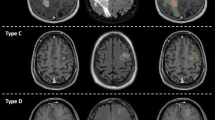

Tumor sub-compartments as defined by the BraTumIA software.

A post contrast abnormal volume (PCAV) was defined as the sum of the necrotic and contrast enhancing volumes. The total abnormal volume (TATV) was defined as the sum of the four sub-compartments: necrosis, enhancing region, non-enhancing region and edema. Note that the non-enhancing tumor region was not manually contoured and therefore the TATV manual was defined as the sum of necrosis, enhancing and edema regions.

A post contrast abnormal volume (PCAV) was defined as the sum of the necrotic and contrast enhancing volumes. The total abnormal volume (TATV) was defined as the entire abnormal signal in the FLAIR images. The edema region (FLAIR envelope) was defined as the difference of the PCAV from the TATV (Fig. 2).